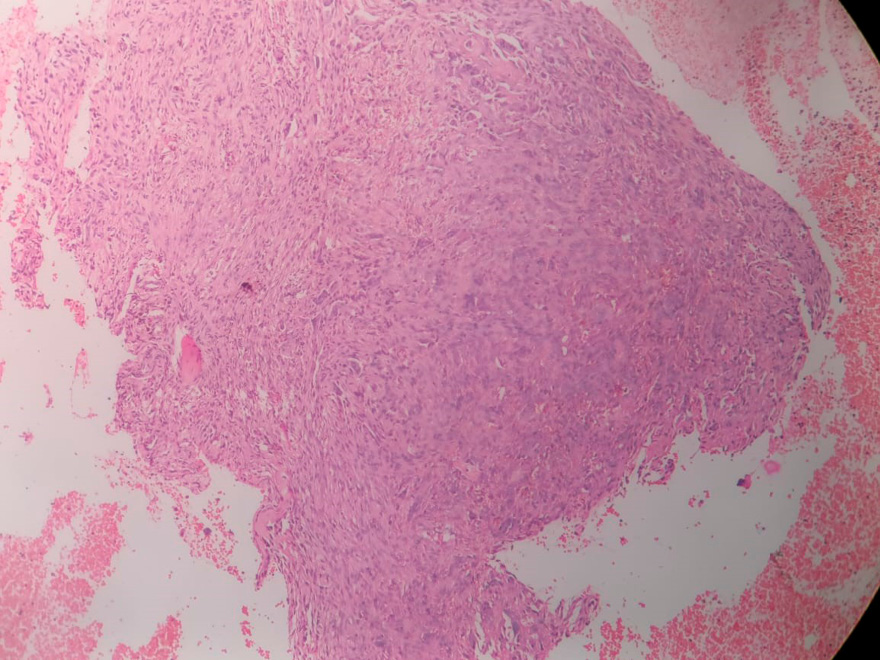

Se realizó una biopsia ósea guiada por TC del hueso ilíaco izquierdo utilizando una aguja Jamshidi. La muestra fue enviada para evaluación histopatológica y citológica. La citología mostró células ovaladas a fusiformes dentro de hebras fibrosas, con leve atipia y sin malignidad. La histopatología reveló numerosas células gigantes tipo osteoclasto en un estroma de células fusiformes fibroblásticas—características consistentes con osteítis fibrosa quística (TM) del hueso ilíaco (Figura 2).

Figura 2.

El análisis histopatológico de la muestra de biopsia mostró numerosas células gigantes dispersas tipo osteoclasto dentro de un estroma de células fusiformes fibroblásticas. Se observan pequeños vasos con glóbulos rojos en su interior. Estas características son consistentes con un tumor marrón del hueso ilíaco